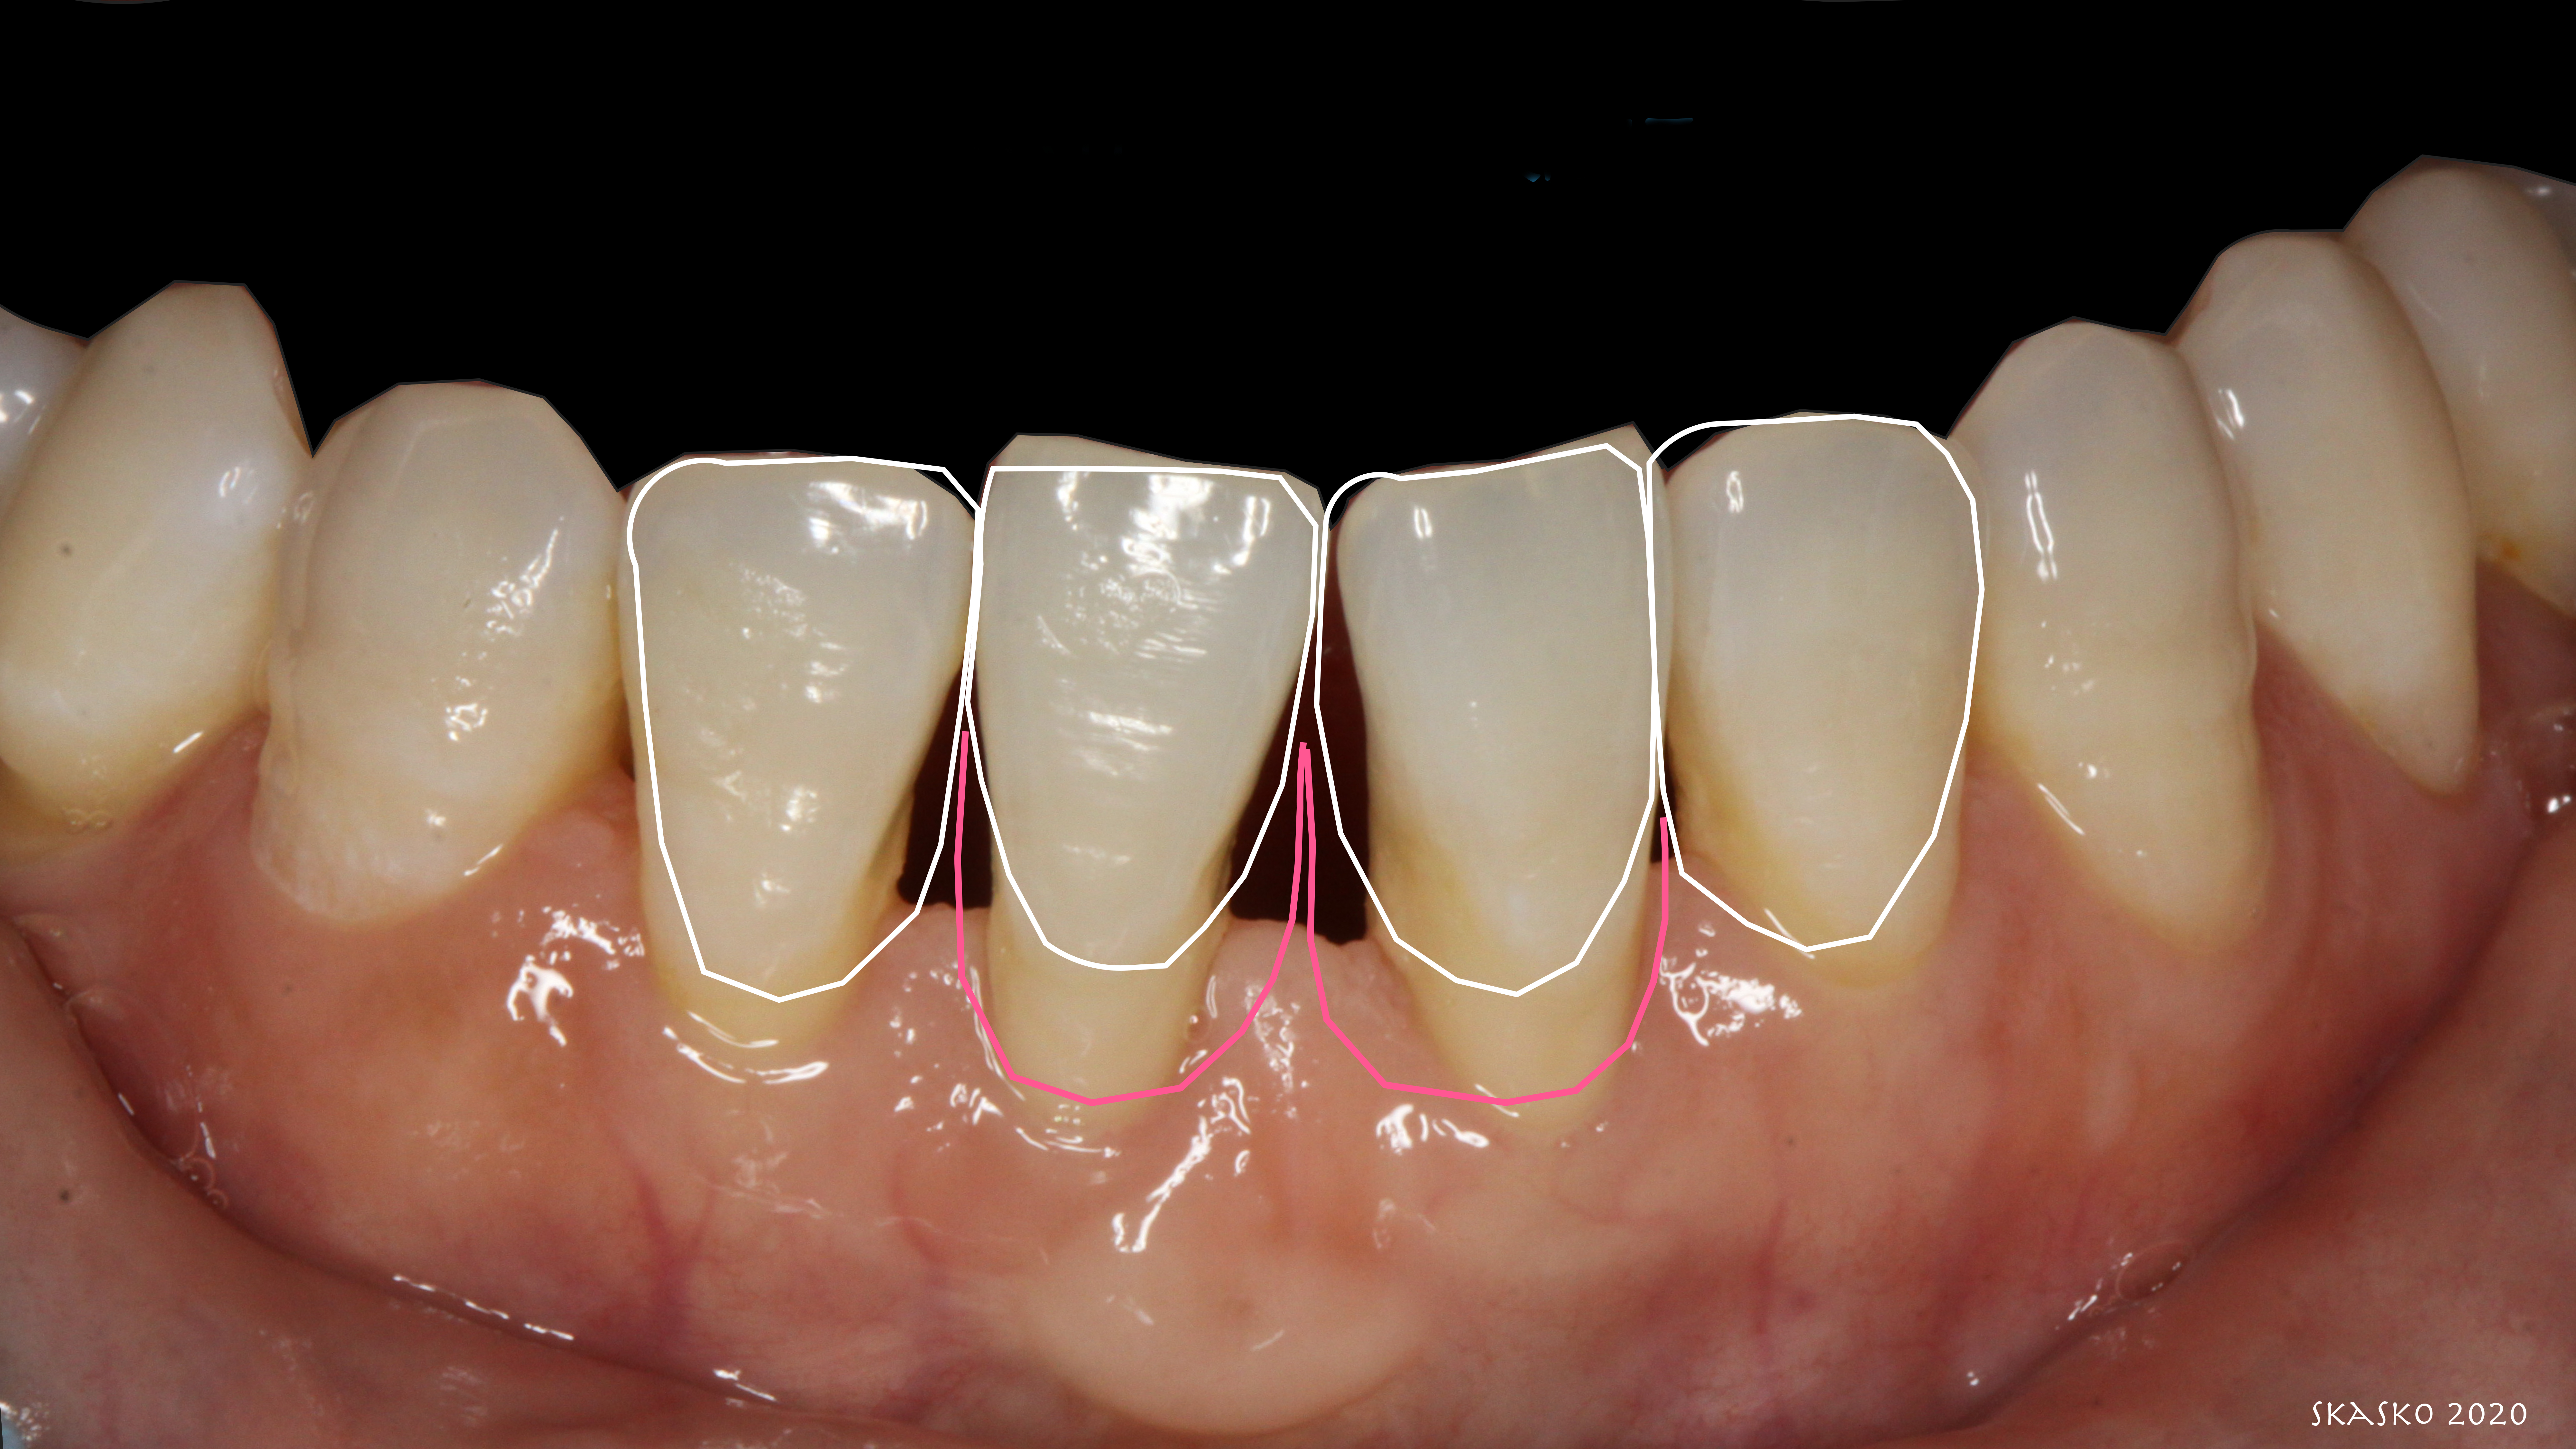

Patient "Jen," age 42, presented with Class III defects (Figure 7) and had previously had a free gingival graft between tooth Nos. 24 and 25. Treatment options were porcelain veneers; porcelain crowns/porcelain bridge after splinting or with removal of tooth Nos. 24 and 25 and pontics; removal of mandibular central mandibular incisors with implant placements (variable placements and restorative options); and composite bonding with or without periodontal splinting.

Fig 7. Patient presents with Miller Class III defects.

Figure 7